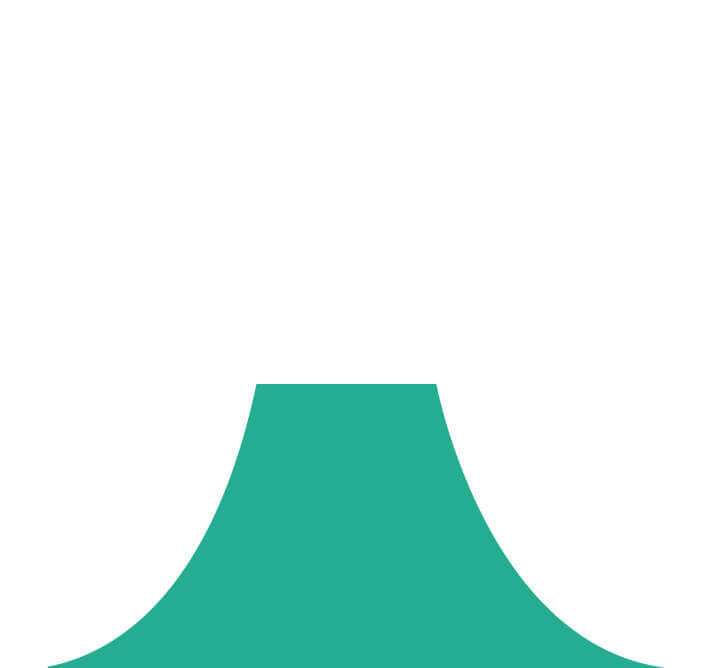

照明光谱

照明光谱

光谱提取

光谱提取

光谱提取能量汇聚

光谱提取能量汇聚

RGB图像重建

RGB图像重建

染色模式显示

染色模式显示